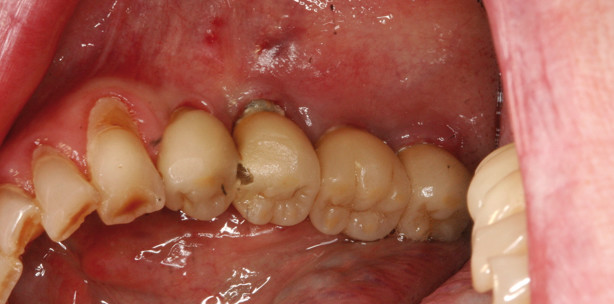

Wir wissen, dass in den nächsten Jahren eine ungeheure Welle an Periimplantitisfällen auf uns zukommen wird. Einige Studien berichten von bis zu 25 Prozent befallener Implantate. Dies ist nicht zuletzt dadurch verursacht, dass Implantate in parodontal insuffizient behandelte Lückengebisse inseriert werden und häufig auch jede Nachsorge fehlt. Momentan herrscht noch keine Einigkeit darüber, welches Therapiekonzept bei einem manifesten Periimplantitisbefall erfolgreich ist und ob es überhaupt gelingt, verloren gegangen Knochen zu rekonstruieren und zu einer Reintegration im Bereich dieser Implantatteile zu kommen. Nur die Vorstufe der Periimplantitis – die Perimukositis – scheint erfolgreich mit verschiedenen Therapiemodalitäten zu behandeln zu sein. Auch hier ist in der Therapie beider Erkrankungsstufen mit PTT mit EmunDo ein Erfolg zu verbuchen. Gerade die Perimukositis lässt sich als Kombination von akribischer mechanischer Reinigung der Implantatkomponenten und Desinfektion mittels PTT sehr gut rehabilitieren. Auch bei etablierter Periimplantitis ist ein deutlicher Entzündungsrückgang der umgebenden Schleimhautbereiche zu bemerken, ohne jedoch den Anspruch zu erheben, damit Periimplantitis geheilt zu haben (Abb. 1 und 2). Ich sehe aber aus Patientensicht den eklatanten Vorteil, eine vielleicht nicht erfolgreiche und invasive Therapie, die häufig die Ästhetik der Implantatrestauration zerstört, gegen eine nichtinvasive und zumindest palliative Therapie einzutauschen. Solange es keine gesicherten Behandlungsvorgaben für die erfolgreiche Periimplantitistherapie gibt, bleibe ich lieber auf der sicheren, nämlich deutlich entzündungsreduzierenden Therapieschiene. Auch hier, wie bei der Parodontaltherapie, stellt EmunDo-A.R.C.-Laser als PTT ein gutes Mittel dar, die vorhandenen Therapiemodalitäten zu erweitern, ohne den Patienten mit unsicheren aggressiven chirurgischen Behandlungen zu belasten.